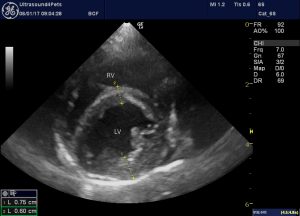

The heart is markedly abnormal:

Subjectively, there is bi-atrial dilation. The right ventricle appears broadly unremarkable (possibly some free wall hypertrophy) but the left ventricle is dilated with a thin-walled and hypocontractile apical part.